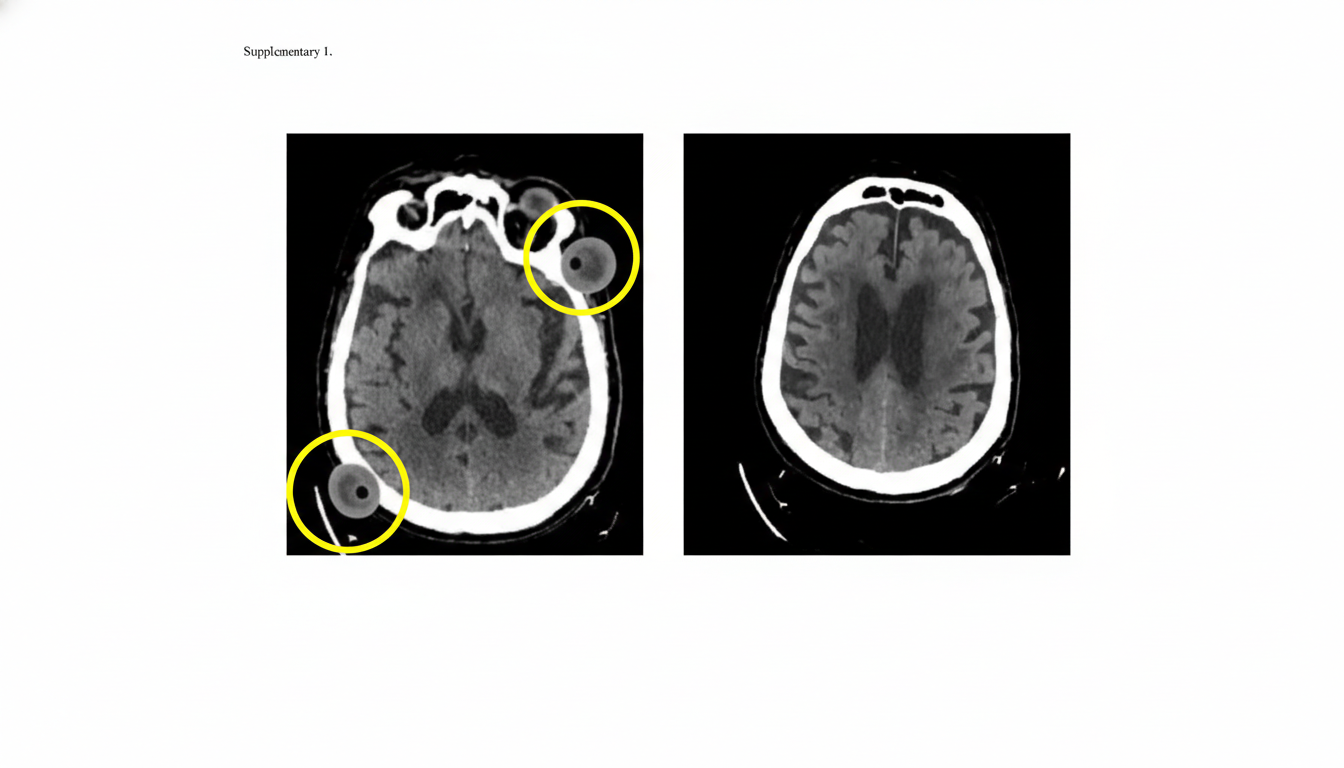

A 60-year-old man is brought to the emergency department by his wife with a sudden onset of right-sided weakness 2 hours ago. He can speak clearly without difficulty and denies any similar symptoms in the past. Past medical history is significant for hypertension and diabetes, both poorly managed due to medication non-compliance. Family history is significant for heart disease and diabetes in multiple paternal and maternal relatives. His vital signs include: blood pressure 150/88 mm Hg, pulse 86/min, and respiratory rate 15/min. On physical examination, strength is 3/5 on the right and 5/5 on the left upper and lower extremities. The sensation is intact, and no impairments in balance or ataxias are present. An initial noncontrast CT scan of the head is unremarkable, but a repeat noncontrast CT scan of the head performed a month later reveals the 2 lesions circled in the image. Which of the following is the most likely diagnosis in this patient?

Explanation: ***Hyaline arteriosclerosis*** - The patient's history of **poorly controlled hypertension and diabetes** are major risk factors for **hyaline arteriosclerosis**, which leads to vessel wall thickening and narrowing, commonly affecting small perforating arteries in the brain. - This condition is a primary cause of **lacunar infarcts**, which manifest as small, deep brain lesions consistent with the patient's presentation of **right-sided weakness (pure motor stroke)** and the later CT findings. *Charcot-Bouchard aneurysm* - These aneurysms are associated with **chronic hypertension** and occur in small cerebral arteries, often leading to **intracerebral hemorrhage** when they rupture. - While associated with hypertension, the clinical presentation here is more consistent with an **ischemic event (lacunar stroke)** rather than hemorrhage, and the CT findings a month later show chronic ischemic changes. *Arteriovenous malformations* - **Arteriovenous malformations (AVMs)** are congenital vascular abnormalities that can present with seizures, headaches, or hemorrhage, but they typically manifest as a **tangle of abnormal blood vessels** on imaging rather than small, punctate lesions indicative of infarction. - The sudden onset of focal neurological deficits followed by the detection of small lesions on CT is less characteristic of an AVM. *Hypertensive encephalopathy* - **Hypertensive encephalopathy** is a serious complication of severe, rapid-onset hypertension, characterized by symptoms like **headache, confusion, seizures, and visual disturbances**, often with cerebral edema on imaging. - The patient's chronic poorly controlled hypertension and presentation of isolated focal weakness, without signs of rapid systemic decompensation or global neurological dysfunction, do not align with hypertensive encephalopathy. *Carotid artery atherosclerosis* - **Carotid artery atherosclerosis** typically causes neurological symptoms through **artery-to-artery embolism** or **hemodynamic insufficiency**, leading to larger ischemic strokes, often involving the cerebral cortex. - The patient's symptoms of **pure motor weakness** and the small, deep lesions seen on follow-up CT are more indicative of a lacunar stroke affecting deeper brain structures rather than a large cortical infarct resulting from carotid emboli.